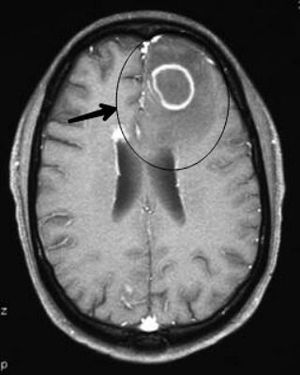

Note the ring-enhanced lesions with surrounding edema arrowed.Toxoplasmosis is an infection caused by toxoplasma gondii. It is seen in immunocompromised patients with CD4 < 100cells/μL blood. The patient will present with mental status changes and seizures. Evaluation is by MRI wirh gadolinium. Medical treatment is pyrimethamine, sulfadiazine, and leucovorin.